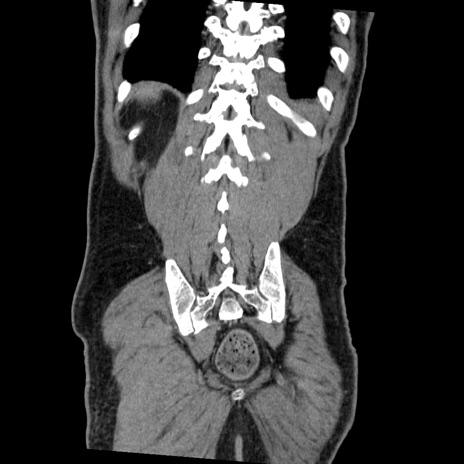

症例22(冠状断像)

【症例】50歳代男性

【主訴】腹痛

【現病歴】AVMからの被殻出血のため回復期リハ病棟入院中。 本日午後3時頃急に下腹部痛が出現した。

【既往歴】AVM、被殻出血、虫垂炎、高血圧

【身体所見】意識晴明、左半身不全麻痺、会話の理解は良好、36.5°C、腹部:膨隆、全体に板状硬、下腹部正中に圧痛点あり、反跳痛-、筋性防御不明、右下腹部にope scar

【データ】WBC 9400、CRP 0.06